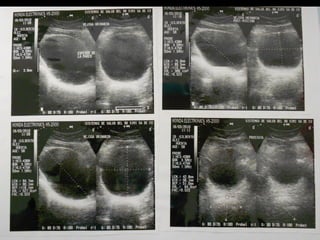

• Uretrografía: sin evidencia de estenosis en uretra penenana o

bulbar.

• Tiene un USG en donde mide la próstat 37x56x60 mm con OR de

110 ml

• Laboratoriales: Valores dentro del rango normal

• PSA Total 2.00